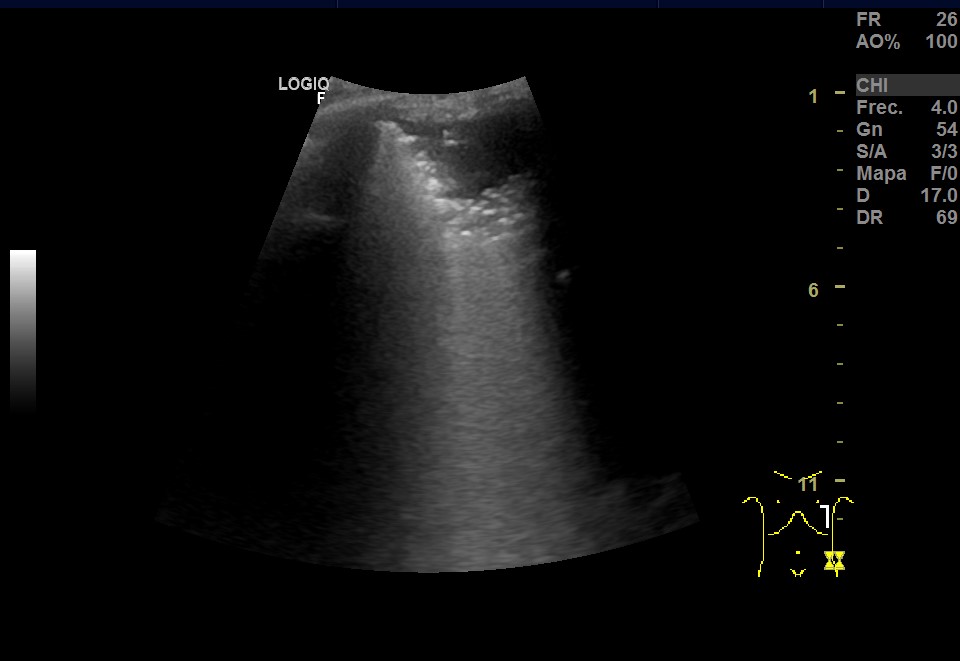

Ecografía pulmonar: imagen hipoecoica irregular subpleural, con signo de desflecamiento, limitada superiormente por la línea pleural e inferiormente por una línea irregular en sacabocados donde aparece un punteado hiperecoico sobre múltiples líneas B que muestran imagen de pulmón blanco. Todo ello sugestivo de consolidación pulmonar con broncograma aéreo. Imagen de medusa sugestiva de pequeño derrame pleural.